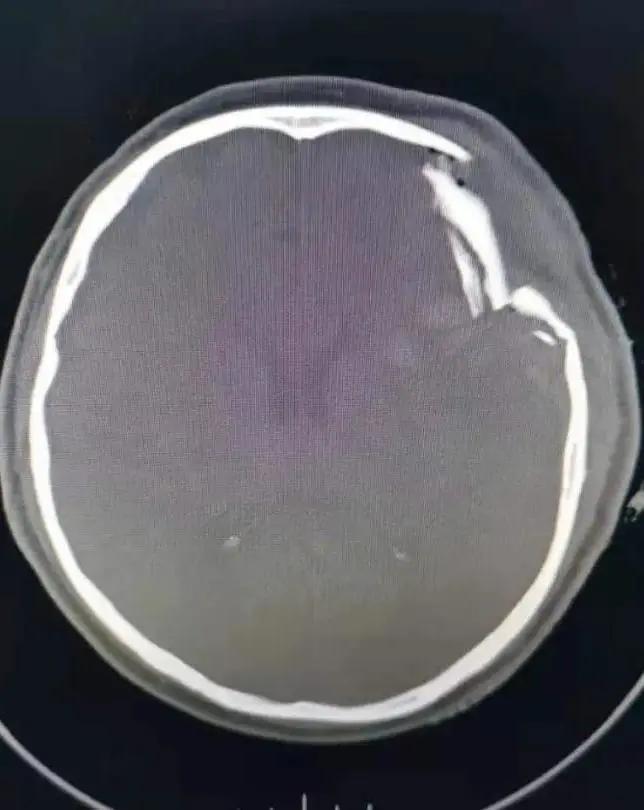

家住萧县白土镇的潘大爷在回家途中,因意外摔伤头部,急到萧县人民医院就诊,头颅CT显示:粉碎性凹陷性颅骨骨折、脑挫伤、脑内血肿。潘大爷处于昏迷状态,左颞顶部挫伤、肿胀,其上有一长约7㎝的伤口,有脑组织外溢,颅骨凹陷明显,病情危急,需急诊开颅手术,事不宜迟,必须争分夺秒。生命重于泰山,面对病人危重的病情,急诊科、神经外科医生响应迅速,立即组织专家进行综合会诊,认为患者情况危急,必须马上手术,在和家属充分沟通基础上,家属同意实施手术抢救。

经过相关检查和评估,在神经外科、麻醉科、手术室等多学科的紧密协作下,神经外科副主任武宏和马涛、纵锋两位医师立即实施手术抢救。虽然夜色已深,神经外科的医生们仍在沉着冷静地进行着一场与时间赛跑的生命拉力赛。经过近3个小时的努力,手术于早上5:05分顺利完成,术后患者转入ICU监护治疗。此次手术风险高,难度大,病人伤情严重,病情危急。医生们面对危急的病情,顺利完成“颅骨碎骨片清除+血肿清除+挫损失活脑组织清除术”,实现了萧县人民医院在颅脑损伤领域新的突破,标志着人民医院神经外科手术水平再次迈向上新的台阶。